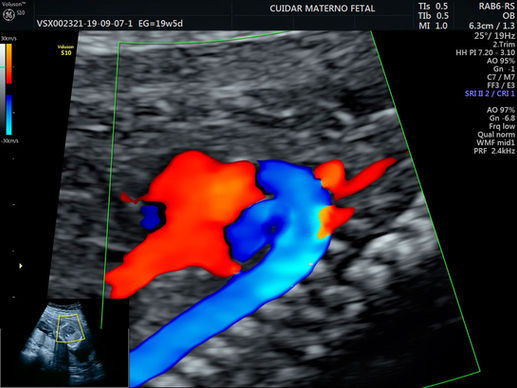

ECOCARDIOGRAFÍA FETAL

Objetivo: evaluar de forma avanzada la morfología del corazón fetal, es muy adecuado para complementar la investigación de patologías fetales intrauterinas.